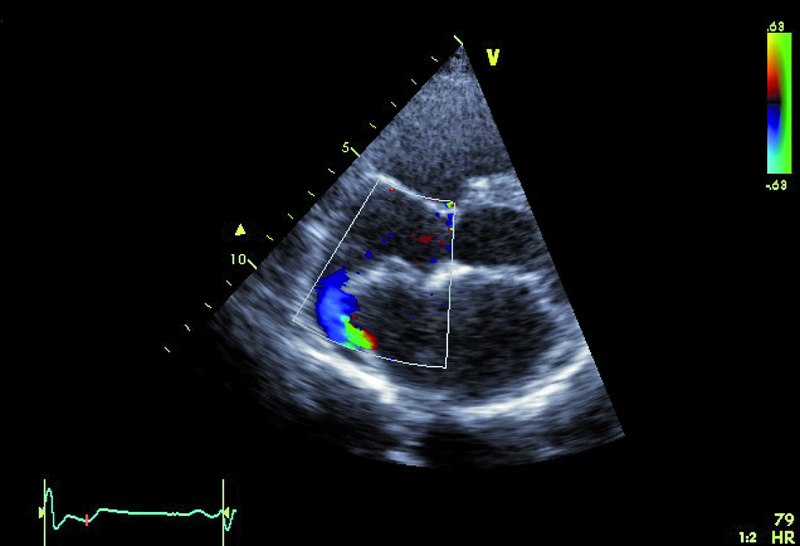

Kobieta, lat 36. Jakie patologie można rozpoznać na zamieszczonych rycinach?

1. Ubytek części błoniastej przegrody międzykomorowej (ryc. 1, 2).

2. Mały przeciek lewo-prawy przez przegrodę międzykomorową (ryc. 1, 2).